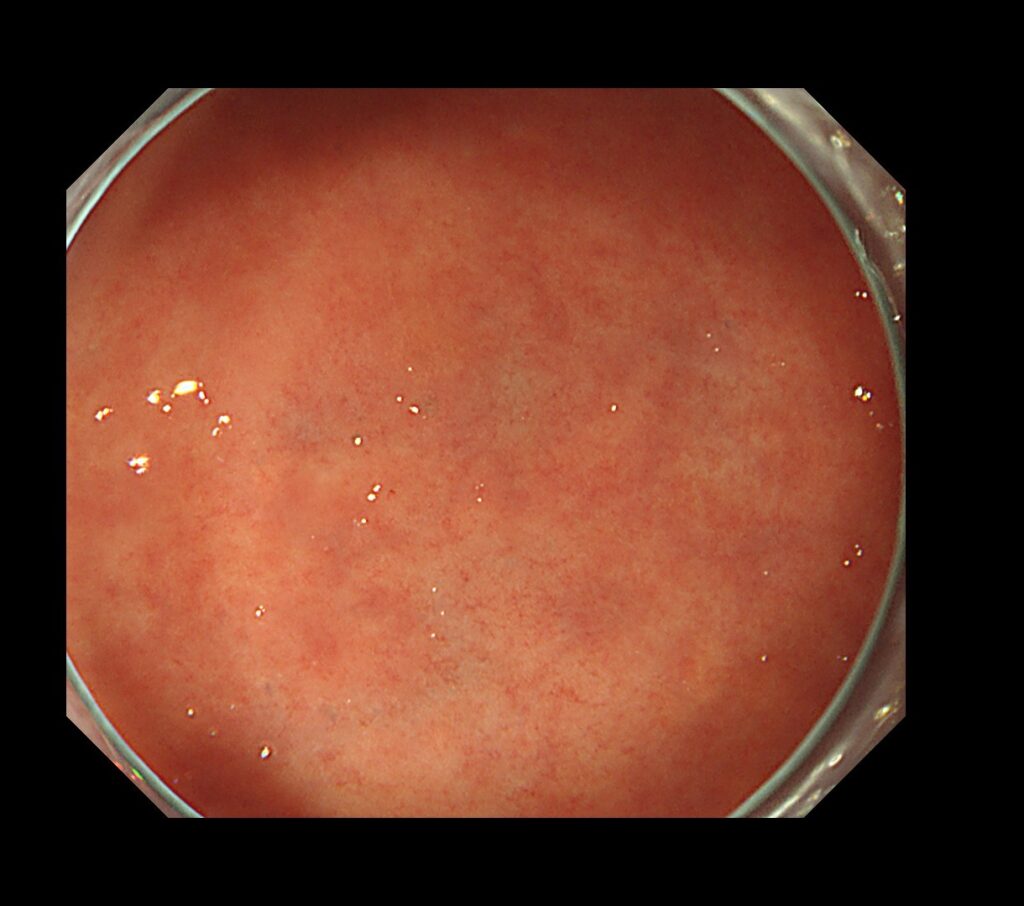

①白色光を用いた通常観察とは以下の写真のように、一般に皆さんが思い浮かべる内視鏡写真です。